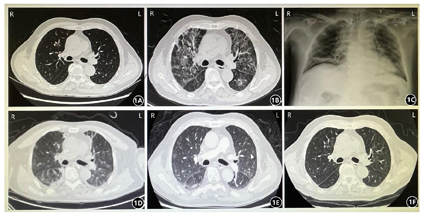

患者男,76岁,因"发热、气促1周"入院。患者于2020年8月24日无明显诱因出现发热,最高体温38.8℃,自感气促,活动后及平卧位明显,休息及坐位可缓解,伴乏力,干咳,口服"尼美舒利"可退热数小时。至当地社区医院予抗感染("左氧氟沙星、头孢米诺")治疗后仍有发热,且气促加重。于2020年8月29日至我院急诊就诊,完善胸部CT,对比起病前我院胸部CT(图1A),现片示:双肺弥漫性改变,感染?肺水肿?双侧少量胸腔积液(图1B);血常规提示白细胞计数10.9×109/L、中性粒细胞计数9×109/L,淋巴细胞计数0.7×109/L,予美罗培南抗感染等处理后,症状较前缓解,最高体温37.7℃,遂于2020年8月30日以"重症肺炎、呼吸衰竭"收入我科。患者既往高血压病史20余年;于2020年6月18日诊断为弥漫大B细胞淋巴瘤,目前R-CHOP方案规律化疗中。无烟酒史、冶游史,家族中无遗传病及肿瘤病史。入院体查:体温36.5℃,脉搏118次/分,呼吸33次/分,血压141/51mmHg。口唇微发绀。双肺呼吸音低,可闻及湿啰音。心率118次/分,律不齐,可闻及早搏,5次/分,双下肢轻度水肿。

入我科后完善血气分析:PH 7.51,PO2 77mmHg,PCO2 27mmHg,BE-0.5mmol/L,FiO2 41%,氧合指数约187;血常规:白细胞计数11.1×109/L、中性粒细胞计数8.8×109/L,淋巴细胞计数1.0×109/L,血红蛋白100g/L,血小板320×109/L;肝功能:白蛋白26.9g/L,谷丙转氨酶98.5U/L,谷草转氨酶113.9U/L;心肌酶:乳酸脱氢酶439U/L;电解质:钙1.97mmol/L;凝血常规:纤维蛋白原7.86g/L;血沉126mm/h,C反应蛋白127.86mg/L,降钙素原1.23ng/mL;B型钠尿肽前体1435pg/mL;T细胞亚群分类:T淋巴细胞(CD3+):627个/μL(62.73%),辅助/诱导性T淋巴细胞(CD3+CD4+):285个/μL(28.53%),抑制/细胞毒性T淋巴细胞(CD3+CD8+): 295个/μL (29.54%);G试验<37.5pg/mL(2020年9月4日复查G试验182.56pg/mL);尿常规、粪便常规、肾功能、肌钙蛋白、输血前四项、病毒全套、甲乙型流感病毒抗原、EB病毒及巨细胞病毒检测大致正常。心电图:窦性心动过速,频发房早,可见差传,T波改变;床旁胸片:双肺感染性病变(图1C)。心脏彩超:肺动脉增宽,主动脉瓣钙化,各瓣膜轻度返流,心室顺应性减退,微量心包积液,右室收缩功能正常(EF:56%)。器官功能评价:APACHE Ⅱ评分:12分,SOFA评分:4分。

患者2020年8月30日11时收入我科呼吸ICU后,气促明显,血气分析氧合指数<200,立即予无创呼吸机辅助通气,同时予复方磺胺甲噁唑(1.44g口服每6小时1次),联合卡泊芬净(首剂70mg静滴每日1次,此后50mg静滴每日1次)抗肺孢子菌治疗,美罗培南(1g静滴每8小时1次)联合莫西沙星(0.4g静滴每日1次)广谱抗细菌、非典型病原体感染、更昔洛韦(0.25g静滴每12小时1次)抗病毒治疗,余辅以营养液、白蛋白营养支持,免疫球蛋白增强抵抗力,PiCCO血流动力学监测,容量控制、保护胃黏膜、抗凝、护肝、护肾等脏器保护、并发症预防等对症支持治疗。此后患者仍发热、气促,氧合指数下降至68,于2020年8月31日10时改气管插管接有创呼吸机辅助联合俯卧位通气(图2A)后,10小时氧合指数上升至150左右,完善支气管镜检查留取BALF送检常规培养及宏基因组下一代测序(metagenomics next generation sequencing,mNGS),结果回报示:耶氏肺孢子菌特异性序列数89条,支持耶氏肺孢子菌肺炎诊断,继续原方案抗肺孢子菌治疗;无巨病毒感染证据,停用更昔洛韦。2020年9月2日,患者体温恢复正常,氧合指数升至270左右。2020年9月4日复查胸部CT示:双上肺、右中肺感染较前吸收,双下肺感染较前稍微增多(图1D),G试验182.56pg/mL,降钙素原2.37ng/mL,继续当前方案治疗,同时予踩单车、带管坐立、拍背排痰等康复训练(图2B,图2C,图2D,图2E)。2020年9月6日复查血气分析示氧合指数297,充分评估后予撤离呼吸机、拔除气管插管,序贯经鼻高流量湿化氧疗(high-flow nasal cannula oxygen therapy, HFNC)(图2F),同时抗菌药物降阶梯为哌拉西林他唑巴坦4.5g静滴每日1次,余方案同前,此后氧合指数维持在400左右。2020年9月8日复查胸部CT示:双肺感染较前吸收(图1E),G试验正常(39.43 pg/mL),降钙素原基本正常(0.279 ng/mL),综合评估前期治疗有效,病变吸收明显,于2020年9月10日停用卡泊芬净,9月14日出院。

患者于出院后,继续口服复方磺胺甲噁唑(1.44g每6小时1次)至总疗程达3周,规律门诊随访,肺部CT示病灶较前明显吸收,未见新发感染(图1F)。